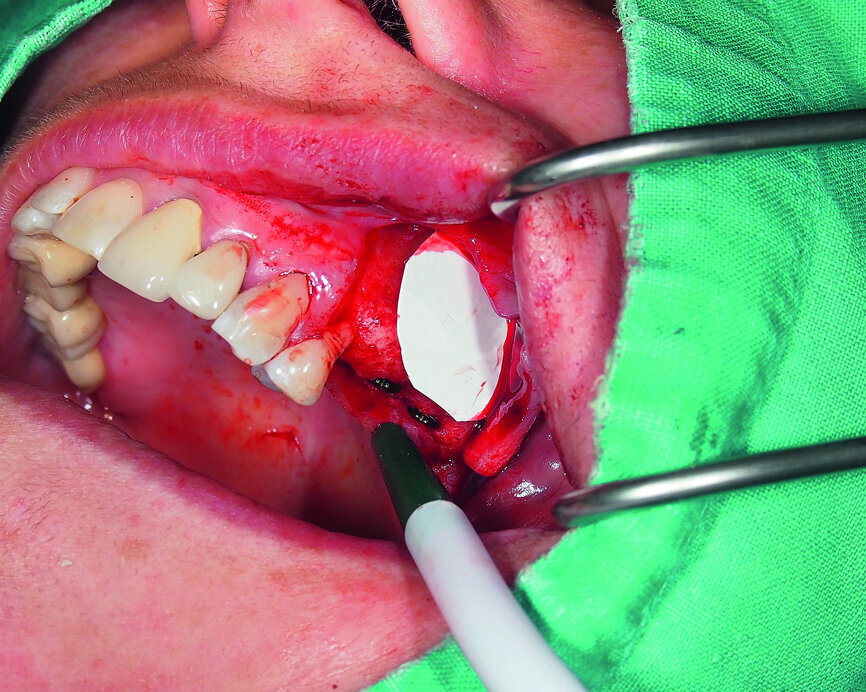

Fig. 6: Facilitation of Schneiderian membrane elevation with a collagenous fleece.

Therefore, we decided to perform a sinus lift by a lateral-wall approach. The Schneiderian membrane was elevated and protected with a collagenous high-density fleece (PARASORB Fleece Genta HD, RESORBA) to allow the placement of a xenogeneic bone graft in the subantral area (Figs. 3–6). Two GC Aadva Standard implants, one of 3.3 mm in diameter and 12.0 mm in length and the other of 4.0 mm in diameter and 10.0 mm in length, were respectively placed in the premolar and molar regions (Figs. 7 & 8). The access window was covered with an absorbable collagenous membrane (PARASORB RESODONT Forte, RESORBA) and the flap was sutured with a polyvinylidene fluoride (PVDF) monofilament suture (RESOPREN 6/0, RESORBA; Figs. 9 & 10).